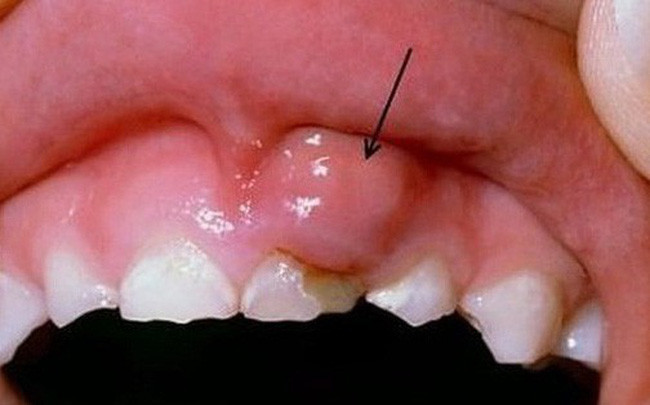

Xuất hiện khối u ở vùng môi hoặc trong toàn bộ khoang miệng, cổ họng cũng là một dấu hiệu của ung thư môi bạn cần lưu ý. Ảnh: dkn.